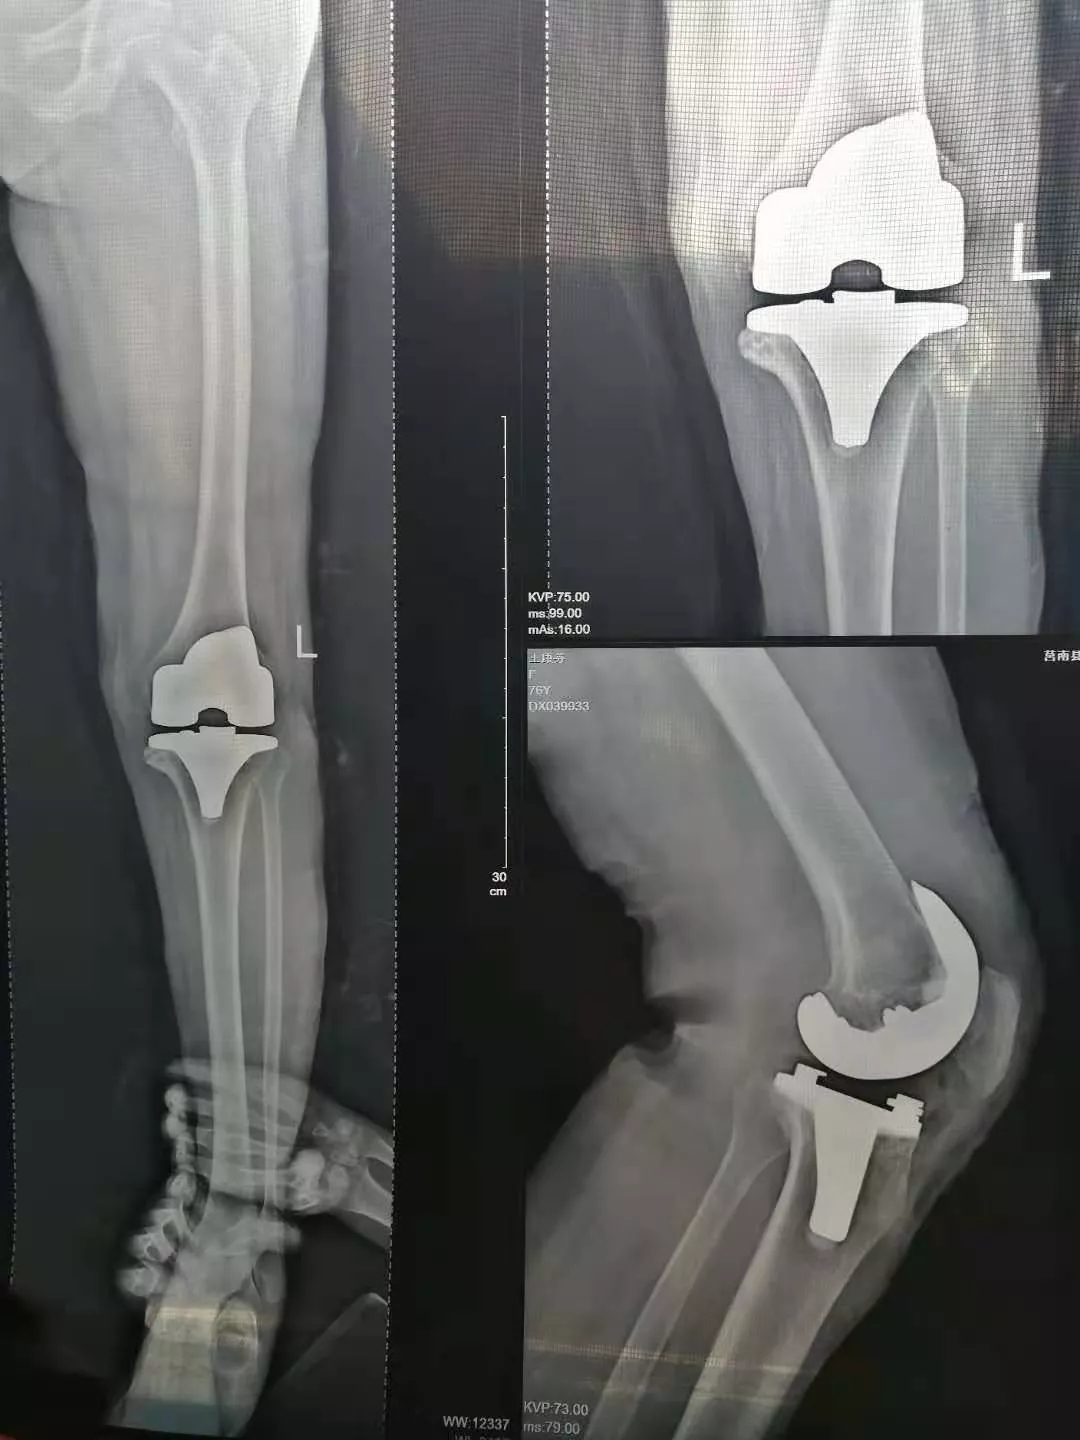

术中处理:双侧间隔一周,均采用股四头肌snip切口入路,术程顺利。术中患膝屈伸活动可达到0°~100°,术后24小时开始屈伸功能锻炼,术后5天屈伸活动达到0°~100°。

术后影像:

于是更改康复计划,强化被动伸膝同时,加强股四头肌力量训练,不再加强被动屈膝训练。术后3个月随访时,患者主被动屈伸膝范围达到0°~100°,左侧伸膝迟滞基本消失,行走时已无度“打软腿”现象。HSS评分左膝85分,右膝88分。